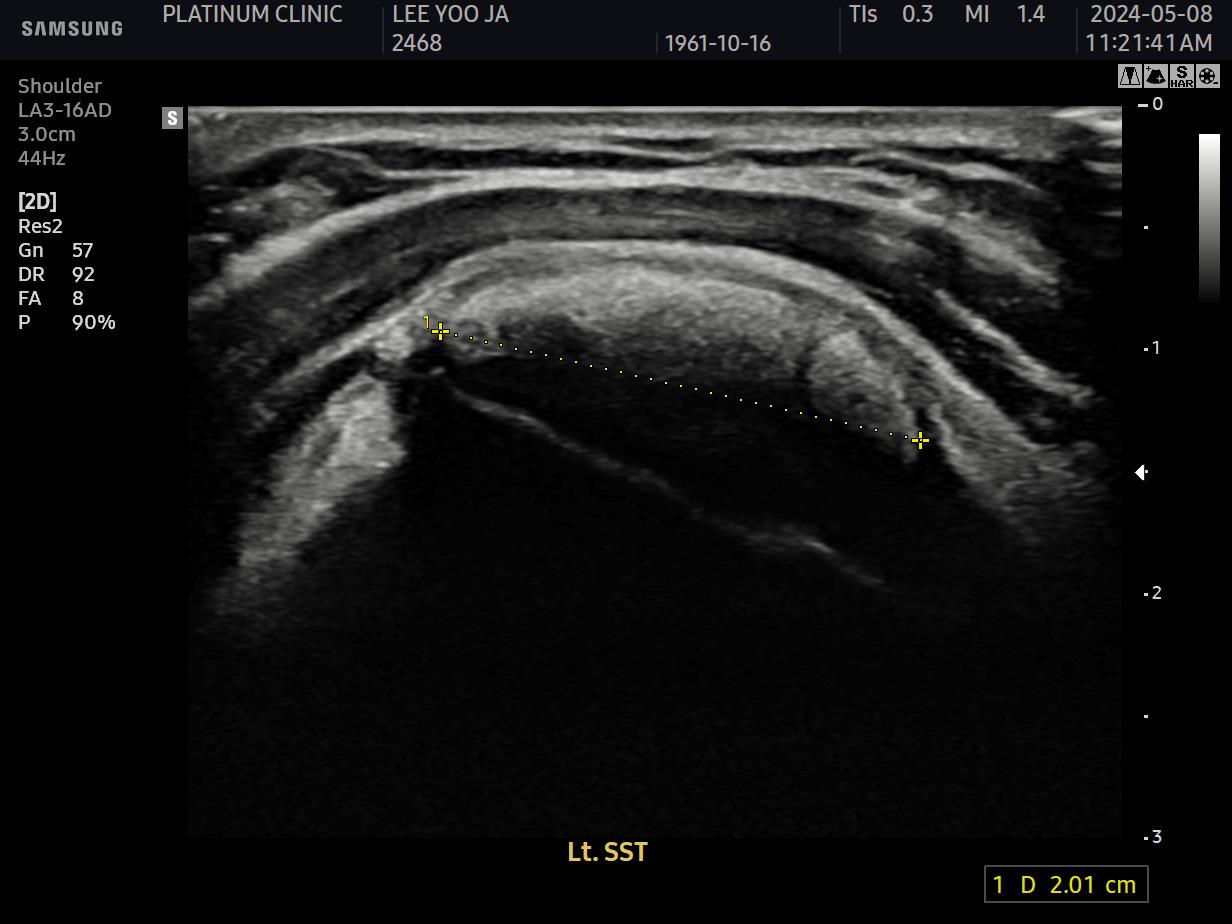

회전근개 힘줄 사이사이에 미세한 석회 침착이 여러 군데 흩어져 있었습니다. 크기가 매우 작아서 3mm 단위로 단면을 촬영하는 MRI에서는 보이지 않았지만, 초음파로는 선명하게 확인되었습니다.

근본 원인인 석회를 제거했습니다. 초음파로 확인된 미세석회들을, 석회분쇄흡입술을 통해 힘줄 사이사이에서 씻어내듯 제거했습니다.

초음파 검사에서도 석회는 깨끗이 사라졌고, 관절낭 유착도 재발하지 않았습니다.